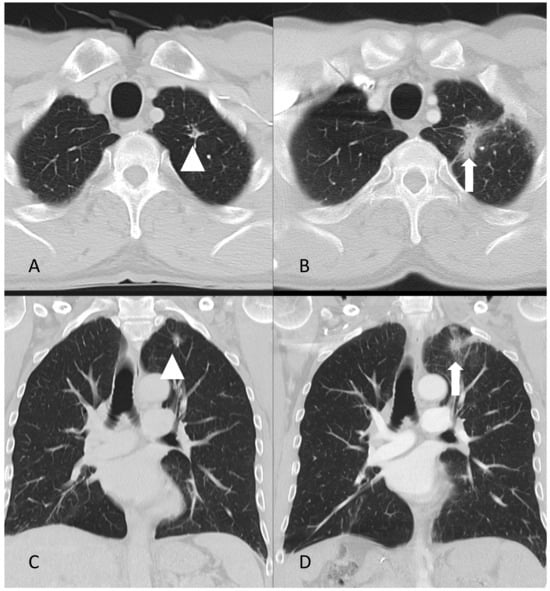

- A case of a patient with AIP type 1 and other organ involvement (bile ducts, testicles, nasal polyps, and lungs) is described.

6. Discussion